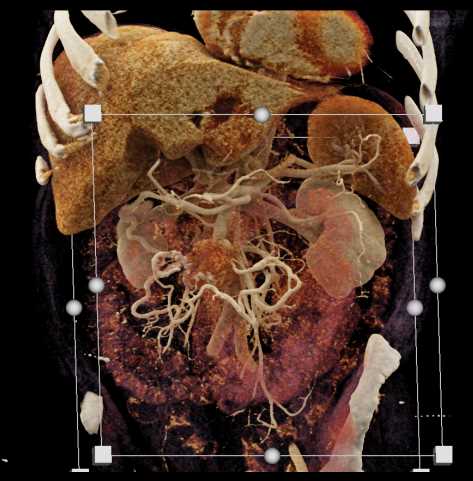

Carcinoid Tumor with Desmoplastic Reaction